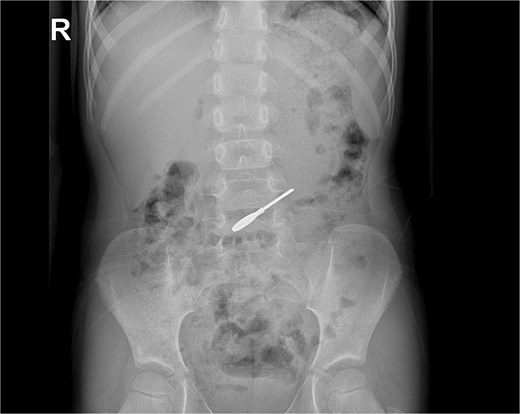

On clinical evaluation, a completely asymptomatic patient was encountered; she was extremely nervous. However, her vital signs were normal, and she had no abdominal pain or tenderness. She passed gas and had no issues with her bowel movements. Due to this, an abdominal X-ray was requested, unveiling a foreign body (small key) in her abdomen. The foreign body appeared to be in her stomach or transverse colon; nonetheless, it did not cause any signs of obstruction (Fig. 1a and b). With these findings, the patient was admitted for close monitoring due to the risk of obstruction. An endoscopy was requested. However, it was completely normal, and the key was nowhere to be found as it had already passed through the pylorus. Another abdominal X-ray was done 48 hours after admission, showing that the foreign body was moving along the intestines (Fig. 2).